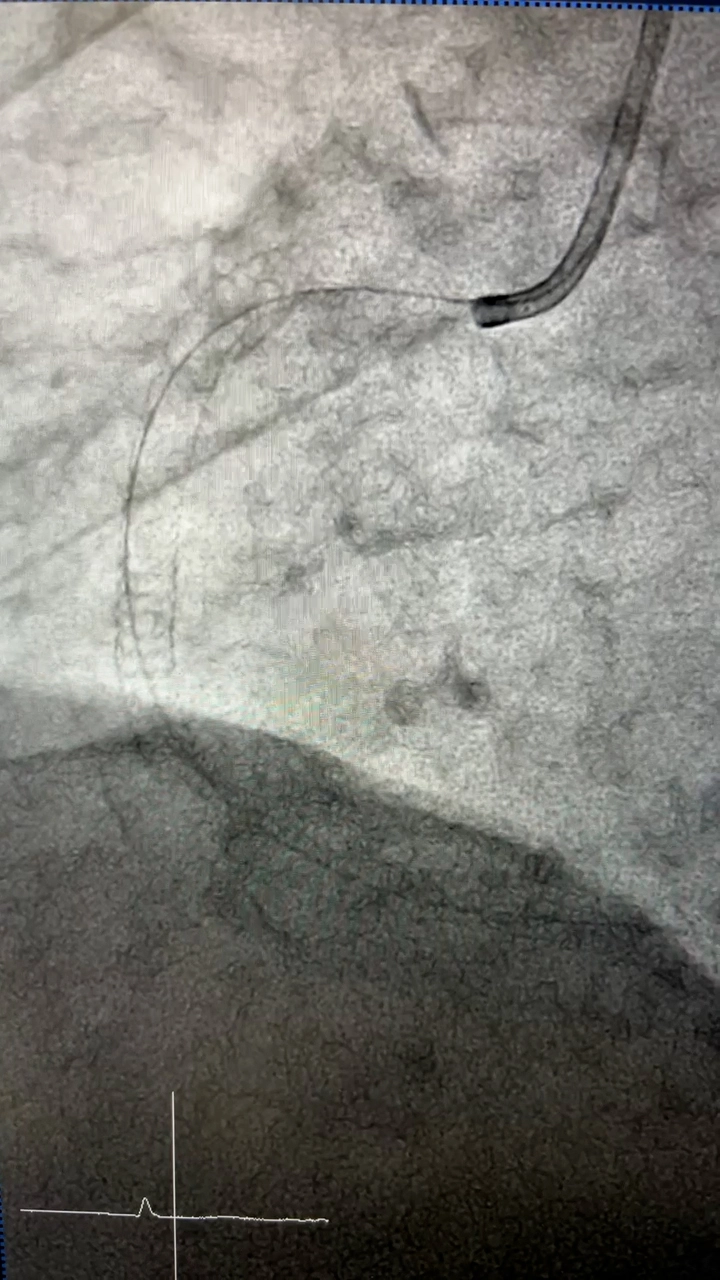

血管造影検査・治療

従来の血管撮影装置よりも、少ないX線量で鮮明な撮影を行なうことができます。心血管検査では一度に広範囲の撮影・診断が可能となり、高精度の検査・治療が行なえます。

また、脳血管検査では脳梗塞の原因となっている血栓の吸引、出血している血管の特定も行なうことができます。

カテーテル検査

検査にはカテーテルという細い管を用いて、血管内に造影剤や薬剤を直接注入することで、狭窄部位や腫瘍などの検索、または治療を行ないます。

心臓カテーテル、血管の3次元画像(3D)など多種にわたって検査することができ、原因疾患の特定にもとても有効な検査です。

検査だけではなく治療も

脳動脈瘤による出血、血栓による脳梗塞、腹部外傷による出血などもカテーテルを使い、わずかな傷で治療を行なうことが可能です。